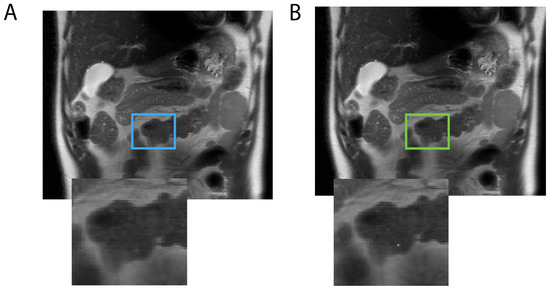

2.2. Annotations

2.3. Agreement Evaluation